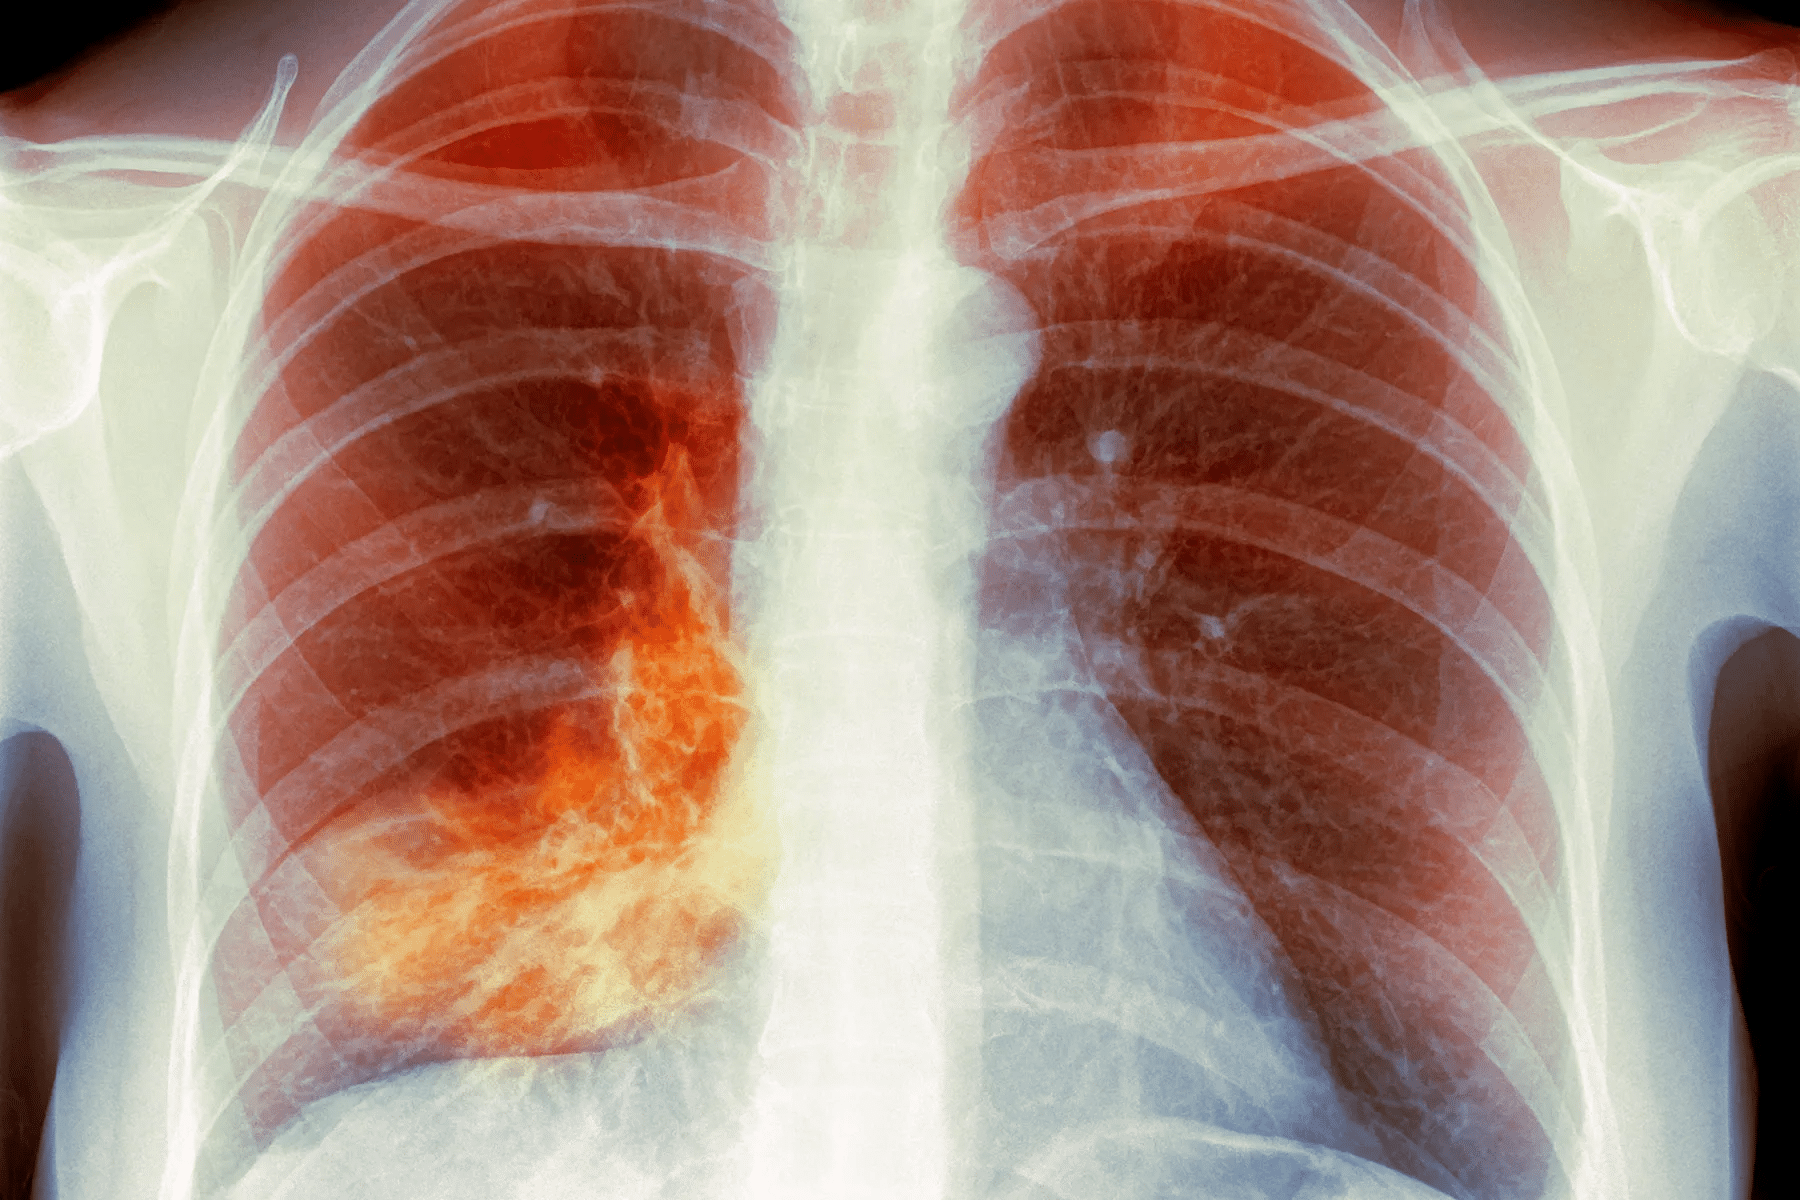

Imaging Tests and Their Importance

Imaging tests, like chest X-rays, are very important. They show lung problems that could be pneumonia.

Chest X-rays help us see patterns of pneumonia. Sometimes, CT scans are used to see more details or find complications.